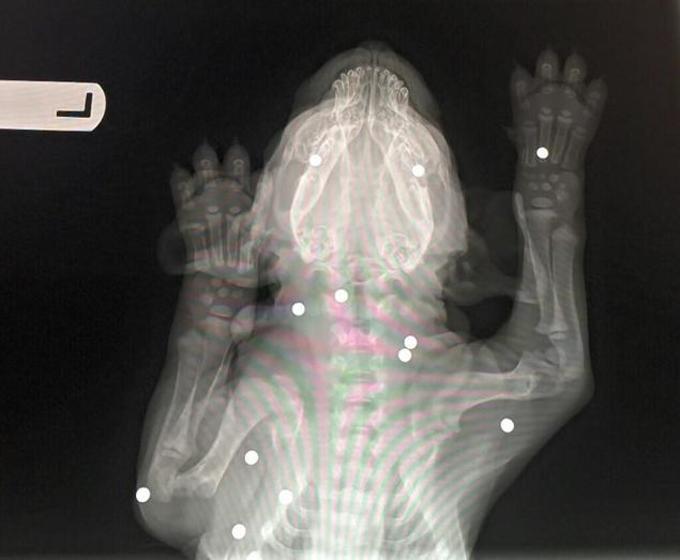

“«Purtroppo è troppo piccolo per essere operato, a sei settimane di vita non sopravvivrebbe all’anestesia – ha detto Jay Hreiz, direttore del centro -. Le pallottole non hanno colpito nessun organo vitale, e in questo è stato molto fortunato. Ma per l’intervento dobbiamo aspettare».